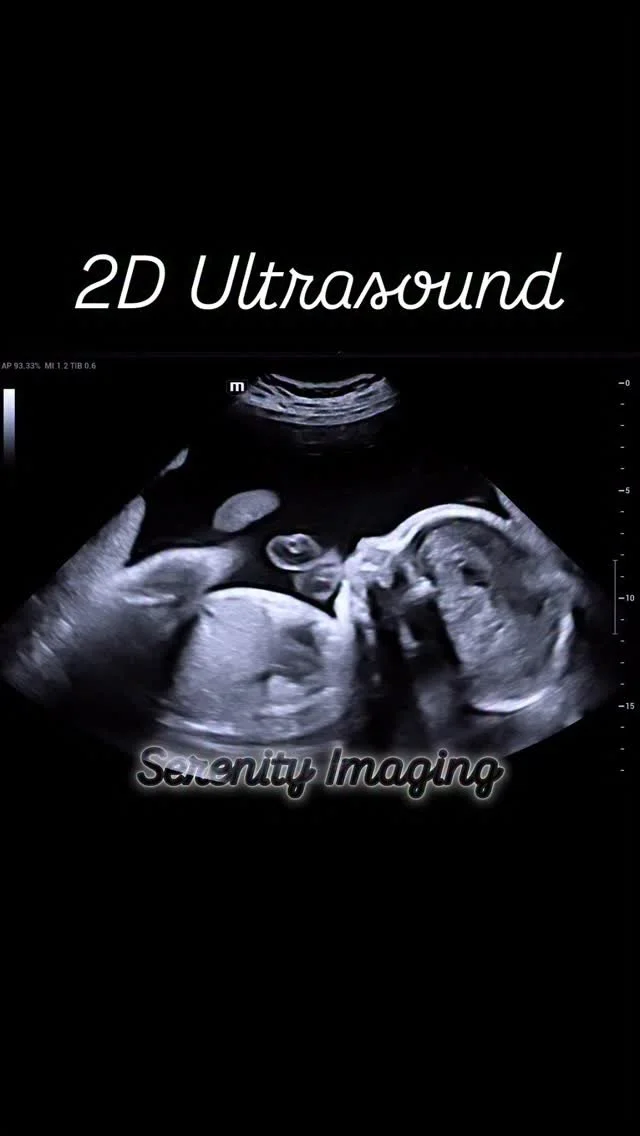

3D/4D/5D baby ultrasound service. We are revolutionizing the way expecting parents can bond with their little ones even before they are born. These advanced ultrasound technologies provide a vivid and lifelike representation of the baby in the womb, capturing charming details that previously remained unseen.

With elective 3D ultrasounds, parents can now see the contours of their baby's face, tiny fingers, and delicate features with astonishing clarity.

These services not only enhance the prenatal experience but also foster a deeper connection between parents and their unborn child. Whether it be preserving cherished memories or sharing the joyous anticipation with loved ones. Elective 3D/4D/5D HD Live ultrasound services offer a remarkable insight into the miraculous journey of pregnancy.